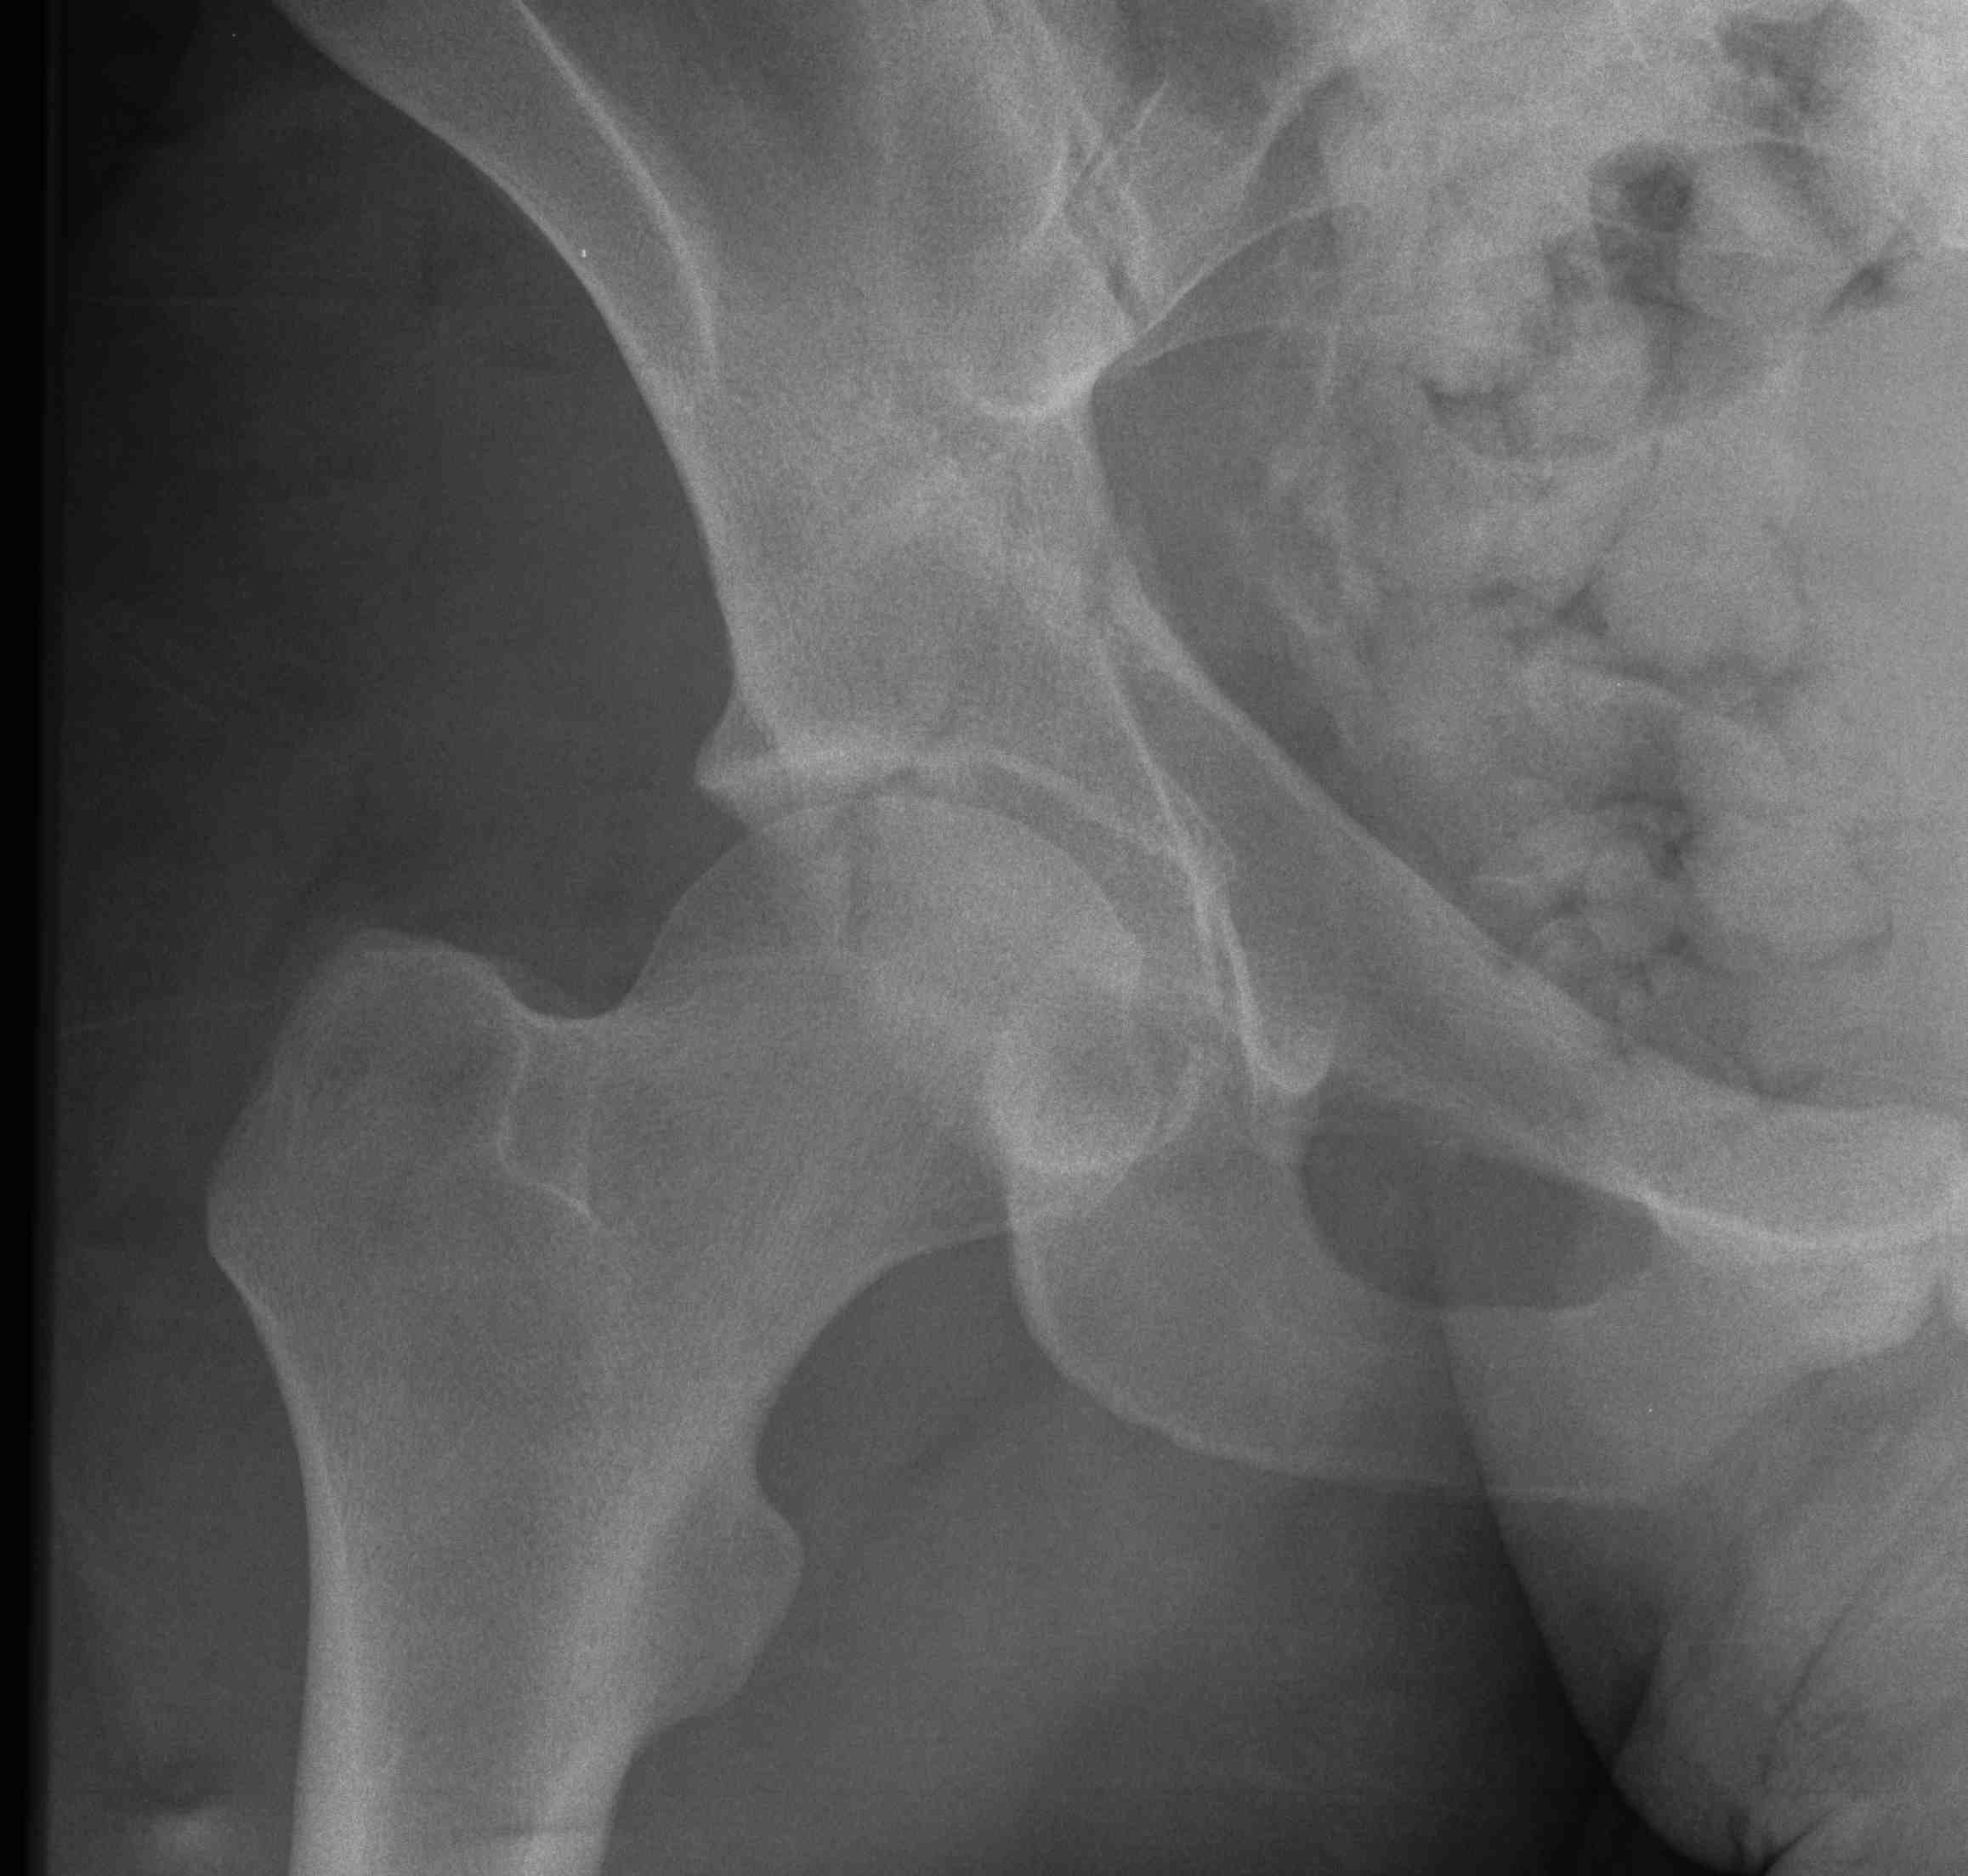

X-ray / 5 standard views

AP / Six X-ray Landmarks

1. Iliopectineal line

- along pelvic brim to pubic symphysis

- anterior column

2. Ilioischial Line

- pelvic brim to ischial tuberosity

- posterior column

- formed by posterior 4/5 of quadrilateral surface ilium

3. The Teardrop

- lateral: subchondral bone condensation at anterior margin of cotyloid fossa

- medial: anterior flat part of quadrilateral surface of iliac bone

4. Roof of acetabulum

5. Anterior rim of acetabulum

- semilunar

6. Post rim of acetabulum